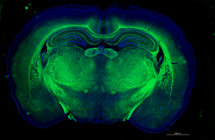

本学獣医学科および獣医保健看護学科では、付属動物医療センターで行う臨床実習を通じて、臨床経験だけでなく、将来、科学的根拠に基づいた治療を行うことのできる動物の医療人を育てます。